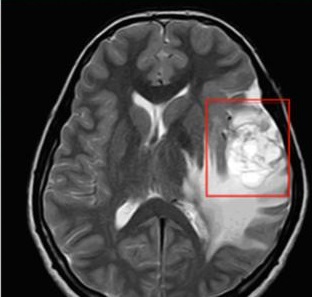

腦癌也可以稱為腦瘤,就是腦袋中出現(xiàn)了一個(gè)不屬于這里的東西,這個(gè)東西可能是在大腦內(nèi)長出的,即原發(fā)性腦癌;也可能是從其他地方跑過來的,即轉(zhuǎn)移性腦癌。